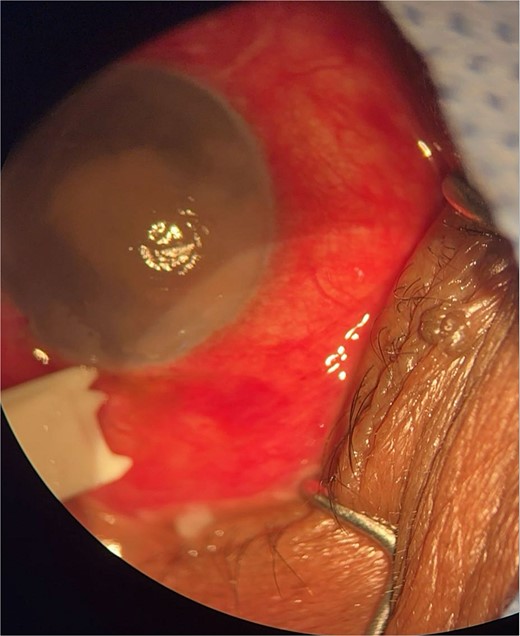

Patient 1: A 66-year-old Sudanese male presented to the emergency room with severe pain in his right eye 2 days post-phacoemulsification. Examination revealed only light perception, elevated intraocular pressure (IOP), a hazy cornea, hypopyon, and extensive pupillary membrane (Fig. 1). A B-scan ultrasound (Fig. 2). He underwent a vitreous tap and received intravitreal antibiotics.

Surgical microscope examination showing hypopyon, chemosis, and conjunctival injection in patient 1.